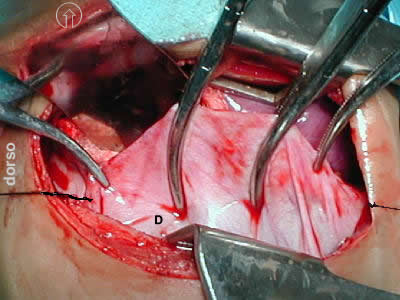

• El abordaje quirúrgico en decubito lateral izquierdo, por toracotomía posterolateral derecha estandar, a la altura del 5to espacio intercostal, esposición de la cavidad toracica, apreciando los siguientes hallazgos:

eventracion diafragma

Figura 1 -

(Cabeza del paciente flecha en circulo)

• LPS: Lóbulo superior pulmonar

• LPM: Lóbulo medio pulmonar

• LPI:  Lóbulo Inferior hipoplásico

• D:  Diafragma derecho

Figura 2 -

D: Cúpula diafragmatica prominente y elevada a la altura de espacio T5, de aspecto muscular y puntos de insercion normal. ocupando gran parte de la cavidad pleural